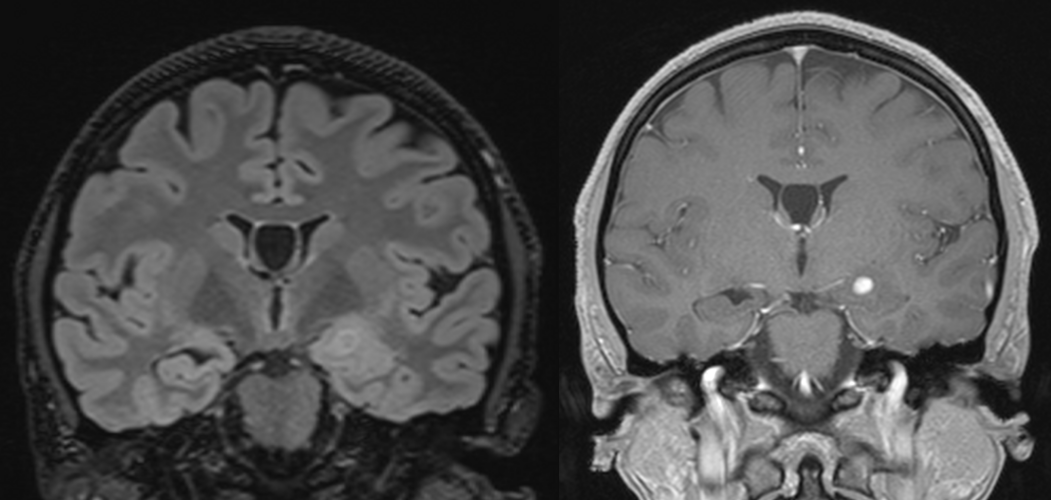

2. DNET (tumora neuroepitelială disembrioplastică)

- Caracteristici: Tumoră corticală benignă, asociată cu epilepsie rezistentă.

- Histologie: Structură nodulară, cu coloane gliale, neuroni displazici și zone mucinoase.

- Localizare: Lobi temporali și frontali.

- Tratament: Chirurgie; prognostic excelent.

- Grad OMS: 1